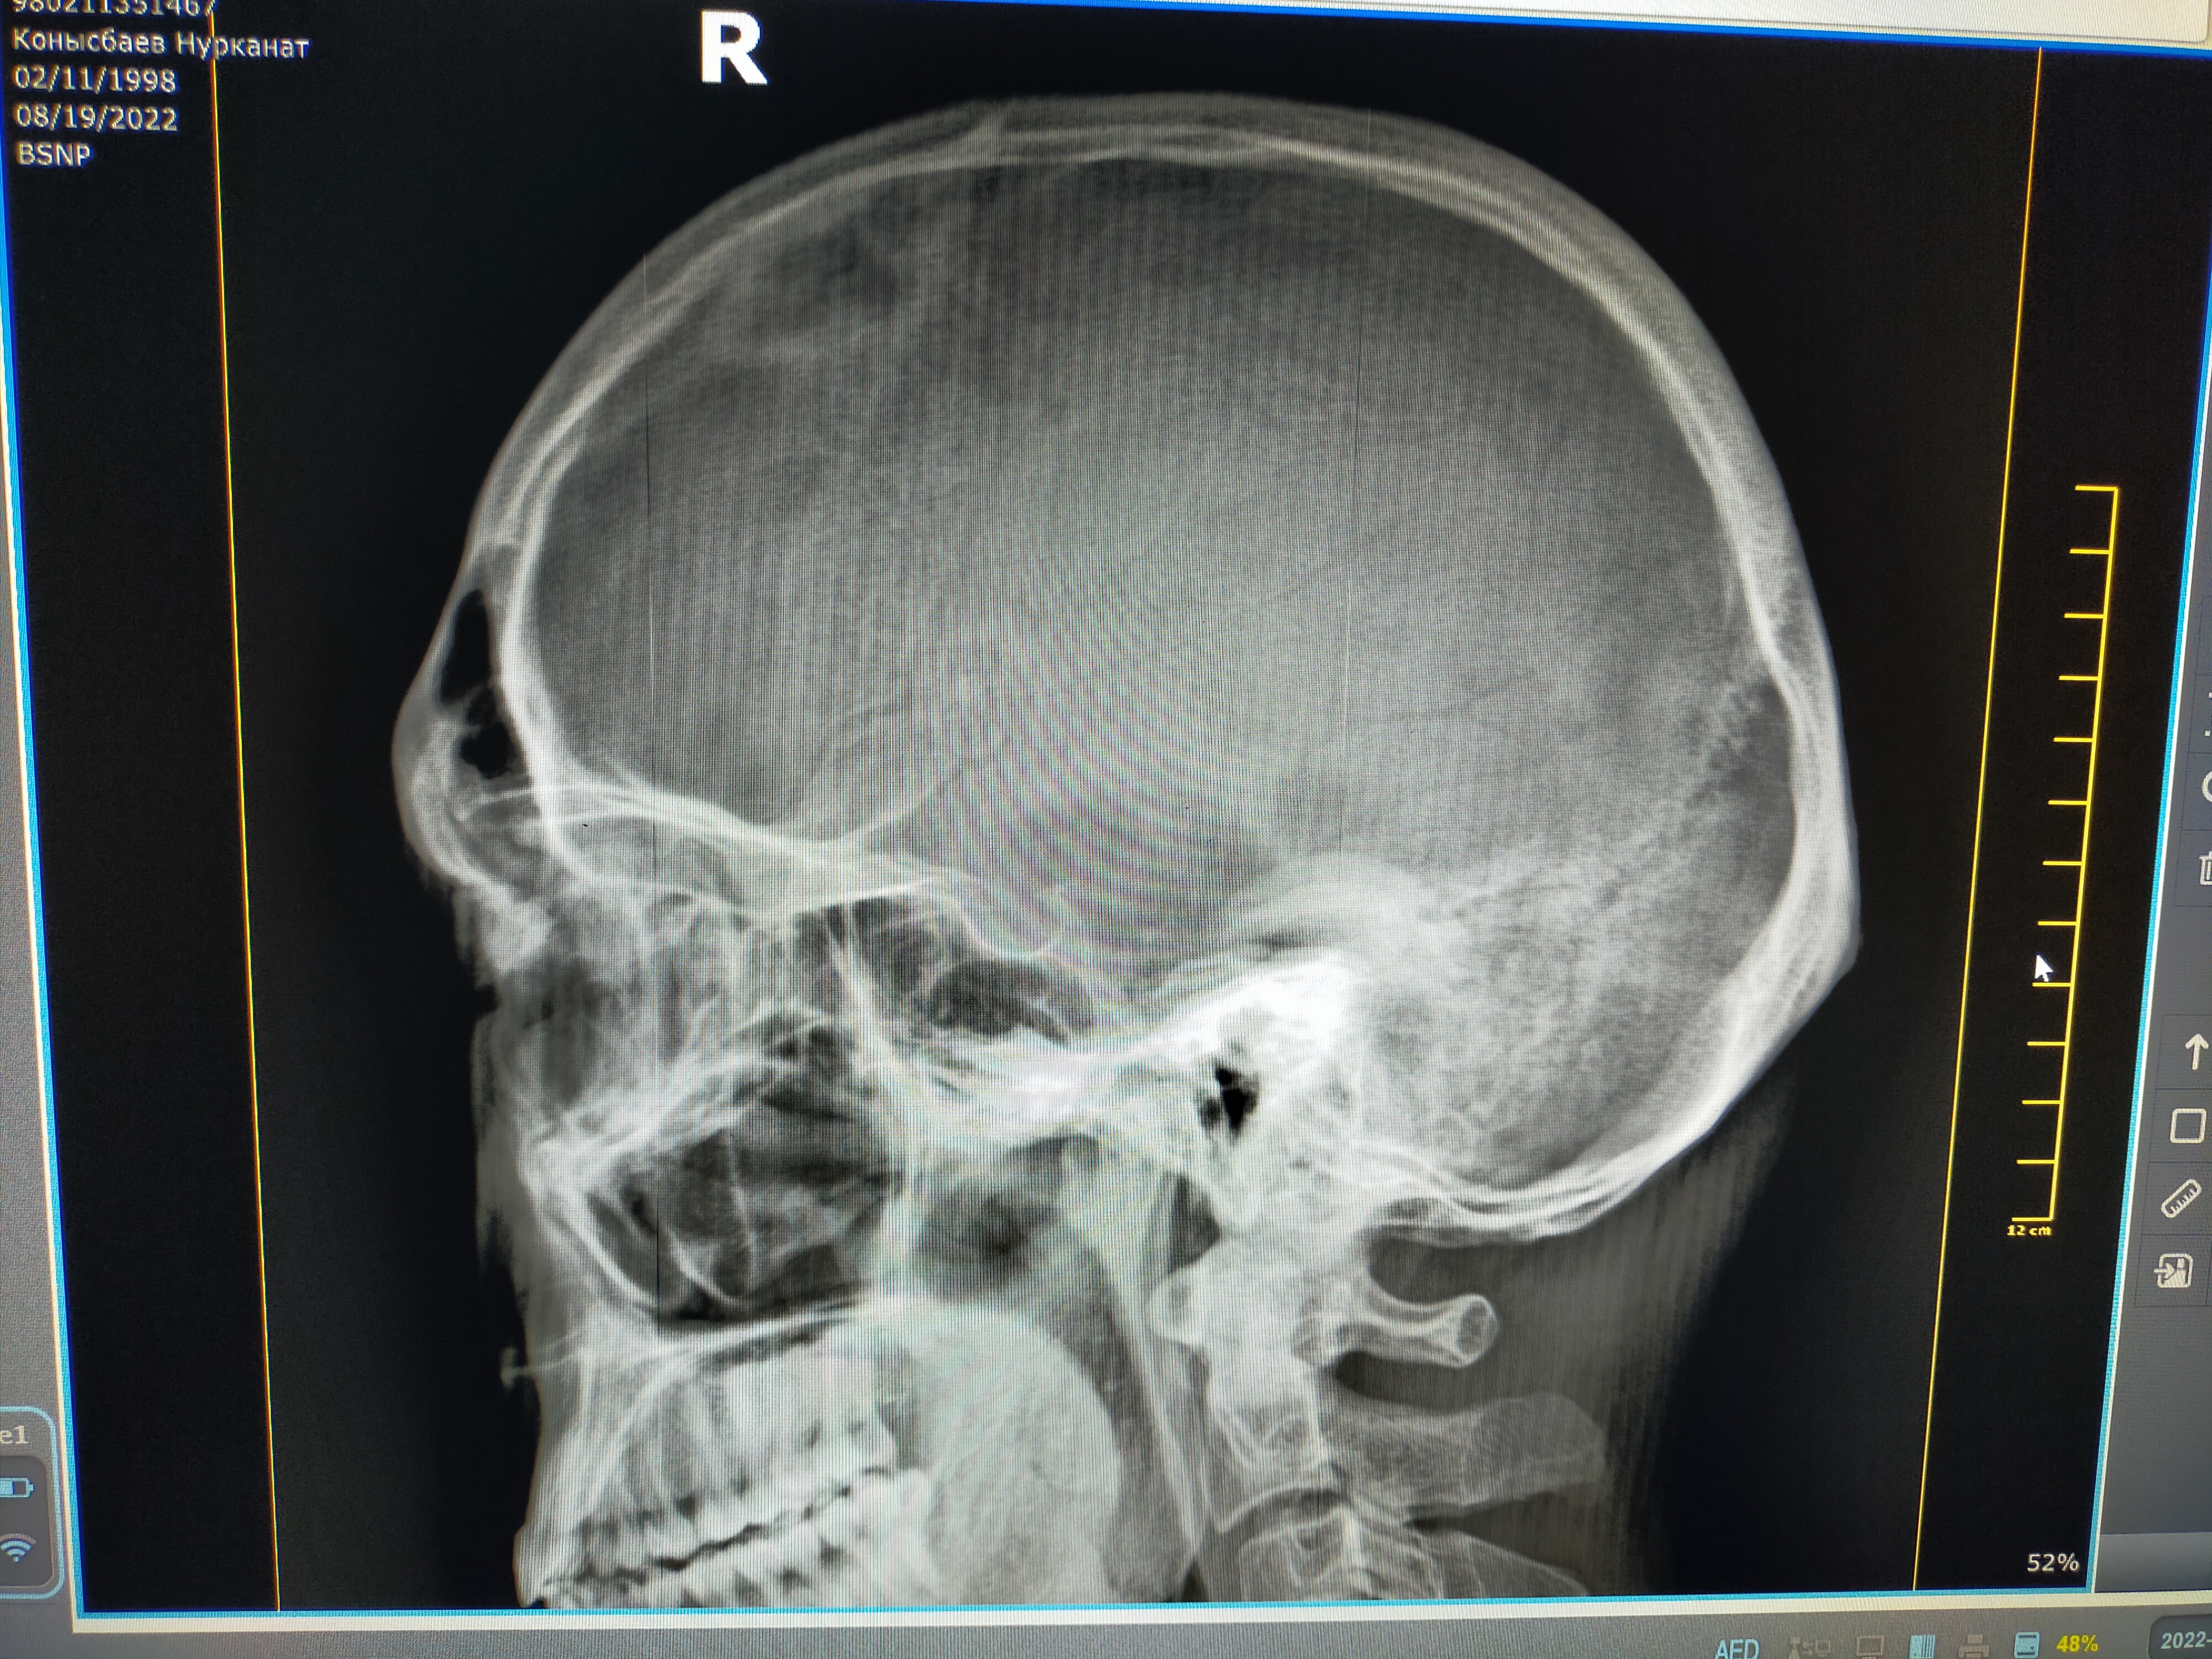

Здравствуйте, коллеги В приемный покой обратился пациент 27 лет с жалобами на головные боли. На рентгенограмме черепа в левой лобно-теменной области определяется кольцевидная тень. Что это может...

Тип: Клиническое наблюдение

Область: Череп и головной мозг

Модальность: Rg

Дата: 19.08.2022 - 08:08